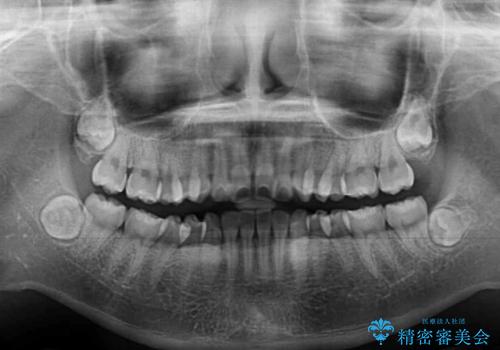

奥歯の咬み合わせを見ると、上顎が下顎に対して相対的に前方にあり、上下の前歯が接触していない状態でした。

咬み合わせを改善するためには、上顎臼歯を後方に移動させた咬み合わせにする必要があります。